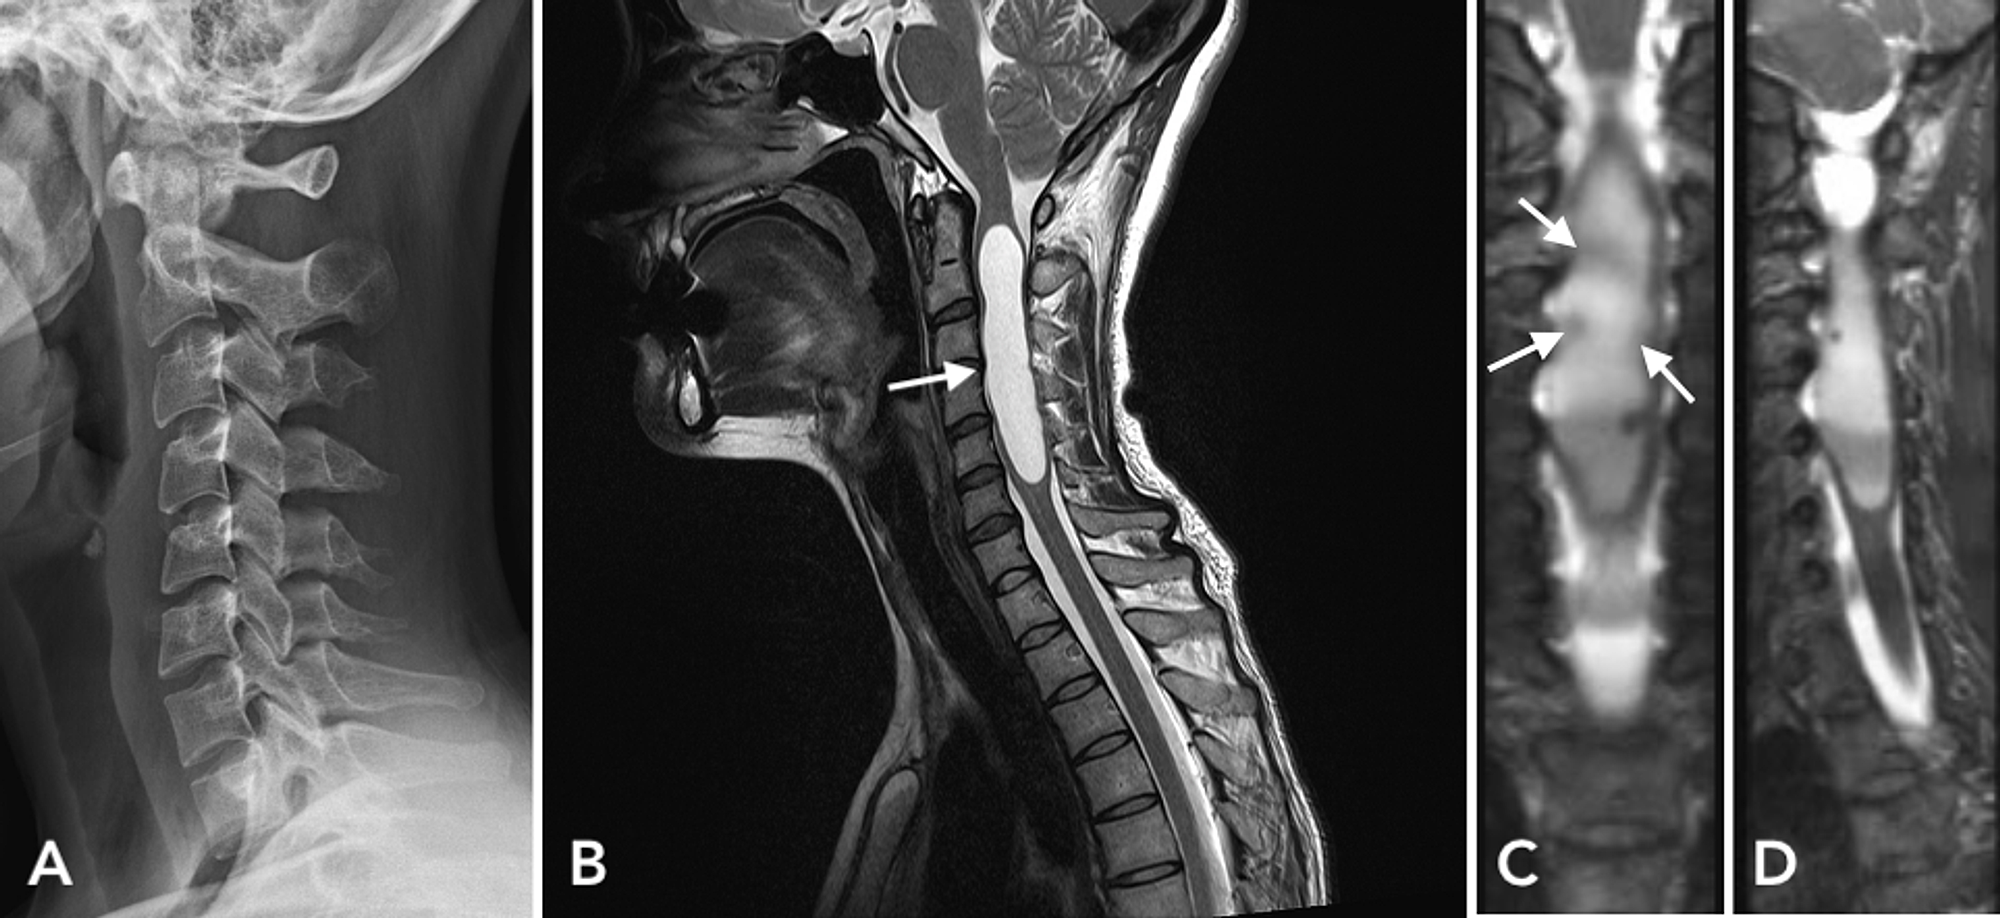

From roentgenrayreader.blogspot.com

Roentgen Ray Reader Posttraumatic Syrinx Can Syrinx Cause Paralysis However, in some cases, the syrinx of syringomyelia can develop due to an unrepaired tethered cord. There are two major forms of syringomyelia: It is thought that if the spinal cord becomes tethered, the pull on the cord can create. This cyst can grow over. For others, syringomyelia will cause. Congenital syringomyelia (or communicating syringomyelia) is most often. Although electromyography. Can Syrinx Cause Paralysis.